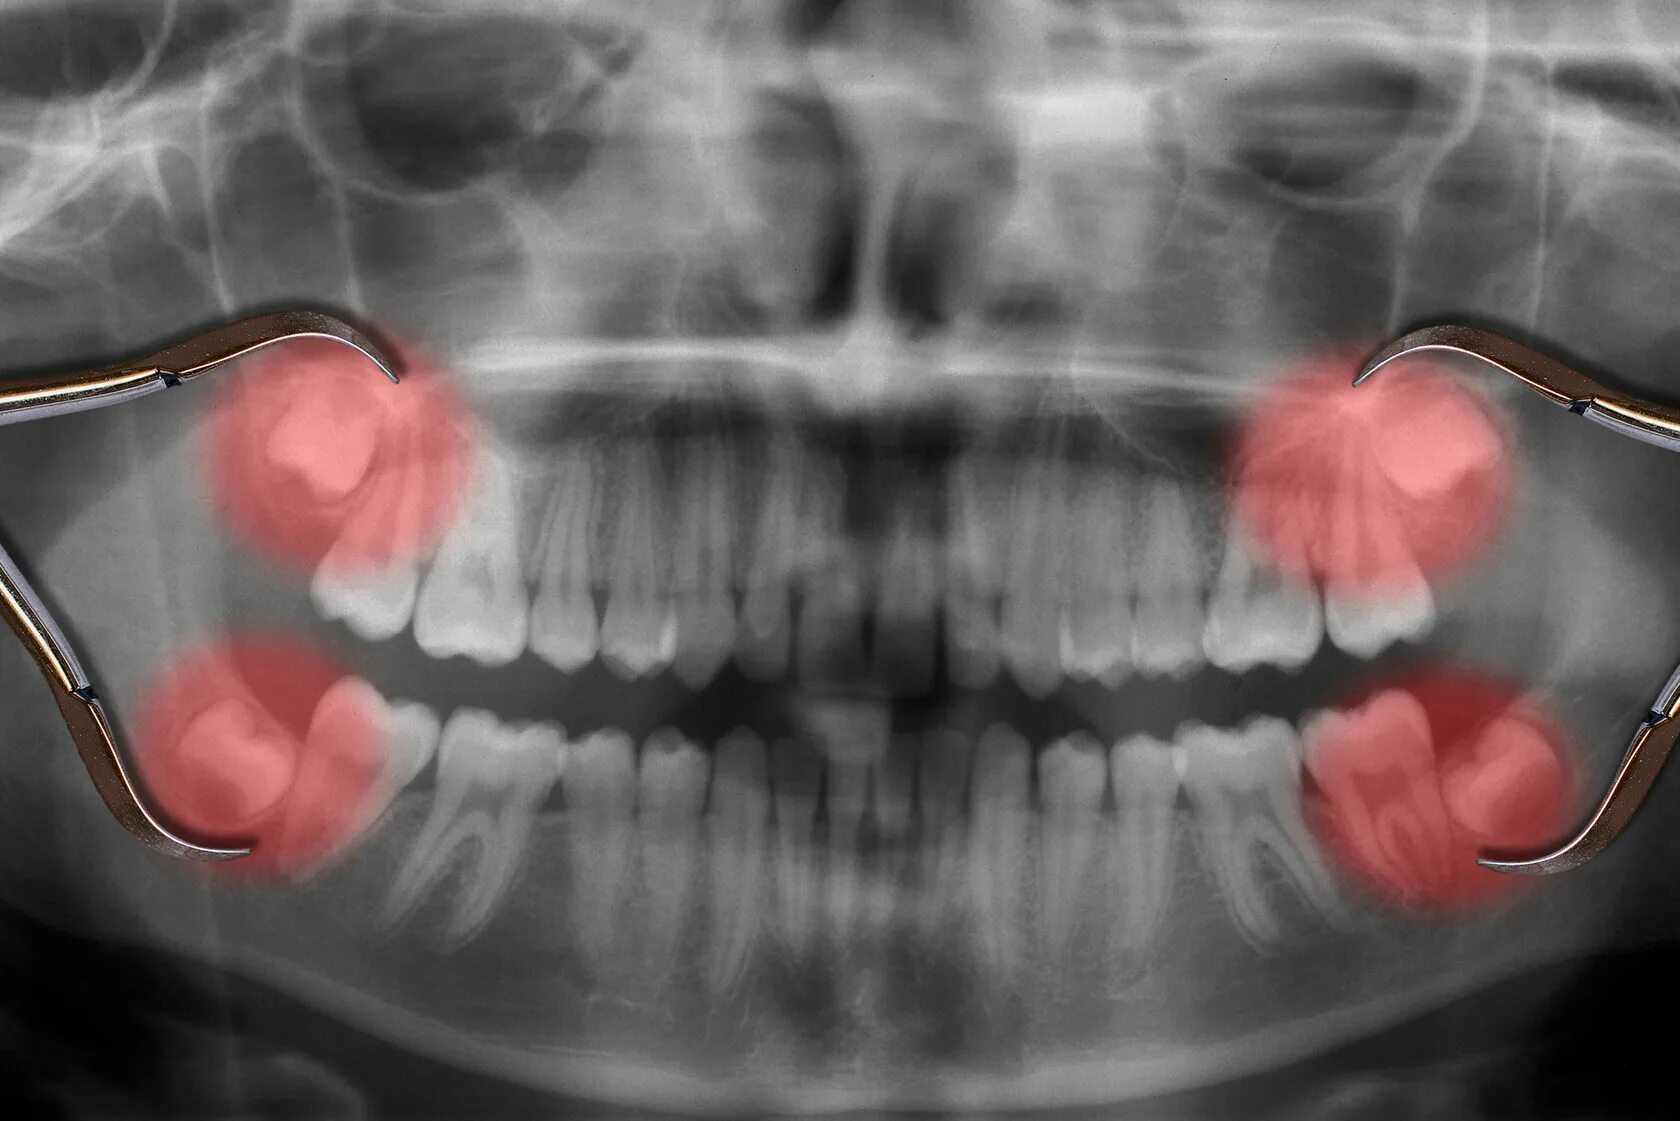

Удалить зубы семерки